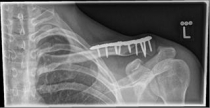

Picture 1                                                                Picture 2

Picture 1: Displaced fracture of the left collarbone before surgery.

Picture 2: After the operation, the fracture is correctly repositioned and held in position with a titanium plate and two screws..